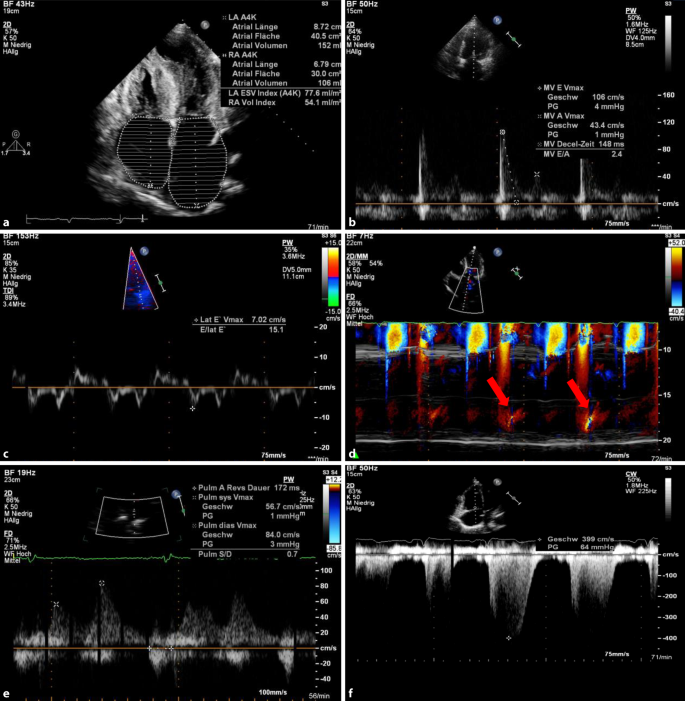

Bettseitige Echokardiographische Evaluation Der Diastolischen Funktion Springerlink

Bettseitige Echokardiographische Evaluation Der Diastolischen Funktion Springerlink from media.springernature.com